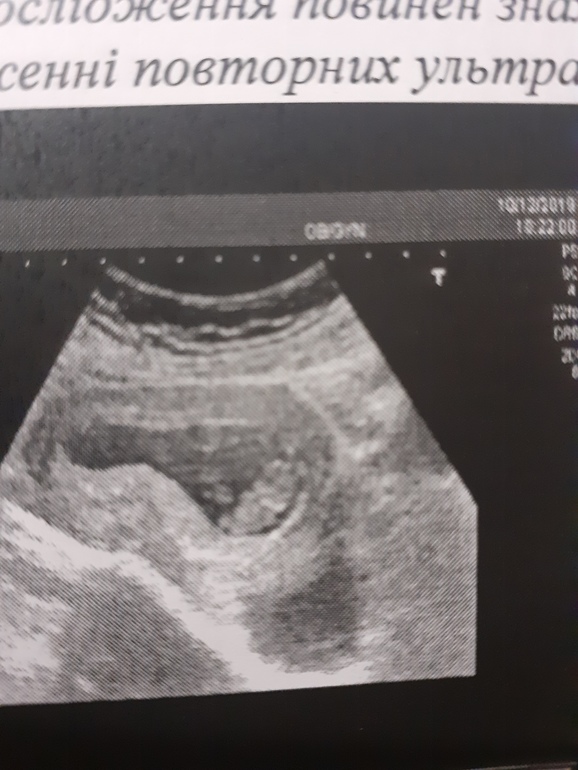

Не всё гладко. к сожалению. Появилась миома, но Г сказала ничего страшного, будем наблюдать. И бесконечный гипертонус, который видимо приводит плодное яйцо в жуткое состояние (на картинке). Я смотрю на фото узи других и вижу, какие у них красивые овальные и круглые домики, а у меня вечно все через ж... Сначала писали ПЯ неправильной формы, потом деформированное, короче какое-то оно странное. Видела вчера на узи как малышу тесно в таком(( Сказали, что пя все равно тоже растет и должно быть всё нормально.